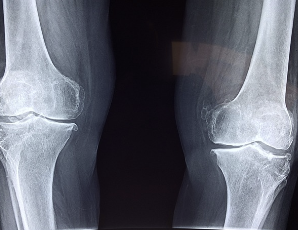

글루코사민 콘드로이친 msm 효능 및 부작용 적정섭취량 등 관련 정보 알아보도록 하겠습니다. 관절은 뼈와 뼈 사이에 위치한 연결점으로, 우리 몸을 움직이기 위한 중요한 부분입니다. 관절은 뼈의 끝에 위치한 연골과 뼈를 연결하는 인대로 이루어져 있으며, 이러한 구조는 원활한 움직임을 가능하게 합니다. 하지만 연령이 들어가거나 부상 등으로 인해 관절의 기능이 손상되면 관절염과 같은 질환으로 발생할 수 있습니다. 이러한 질환은 관절 통증, 감각 이상, 염증 및 손상 등을 일으키며, 일상생활에서의 움직임과 활동에 지장을 주어 생활의 질을 저하시킵니다. 이에 따라 적절한 치료와 예방이 필요하며, 영양소와 운동 등을 통한 관리가 중요합니다.